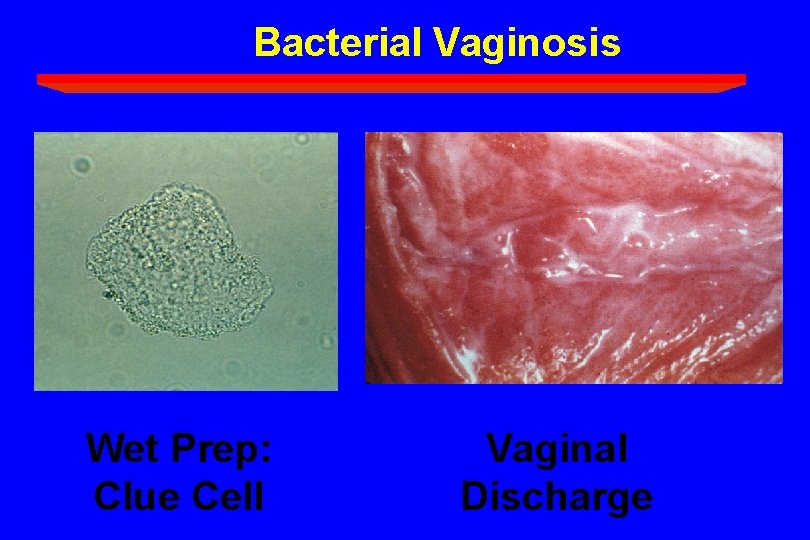

Diagnosis of BV · Clinical findings (Amsel criteria): >3 of the following: - Homogeneous discharge, smoothly coating vaginal walls and - introitus p. H >4. 5 Clue cells (>20%) on saline microscopy Amine odor on addition of KOH (+whiff test) • Putrescine, cadaverine • BV Blue® test: uncertain clinical utility · Gram stain findings (Nugent scale) - Based on number of lactobacilli and other bacterial - morphotypes 0 -9 scale: 0 -3 normal, 4 -6 borderline, 7 -9 definite BV Primarily research, but clinically useful in trained hands

Bacterial Vaginosis Wet Prep: Clue Cell Vaginal Discharge